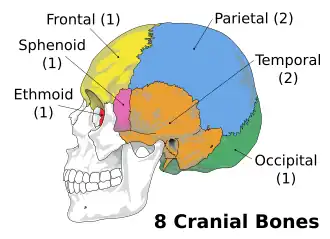

The eight bones that form the human neurocranium. | |

The eight cranial bones. (Facial bones are shown in transparent.)

Yellow: Frontal bone (1)

Blue: Parietal bone (2)

Purple: Sphenoid bone (1)

Brown: Temporal bone (2)

Green: Occipital bone (1)

Red: Ethmoid bone (1) | |

In humans, the neurocranium is usually considered to include the following eight bones: